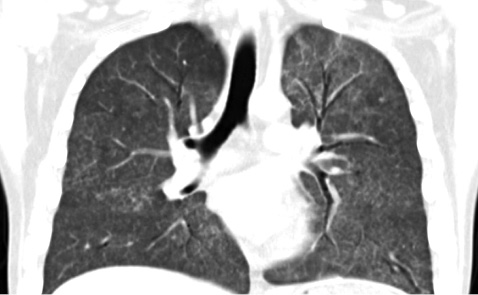

Пациенту К. была проведена инфузия ритуксимаба по 1000 мг дважды с 2-недельным перерывом между введениями (15.08.2017 г. и 01.09.2017 г.) на фоне продолжающейся терапии пероральными глюкокортикоидами. Отмечено существенное улучшение как клинического состояния пациента, так и лабораторных показателей. У больного остановилось кровохарканье, возобновилась способность к спонтанному дыханию (пациент был отключен от СРАР-терапии на 5-й день после первой инфузии ритуксимаба), в том числе при обычных физических нагрузках, исчезла одышка в покое и при физической нагрузке, при аускультации легких — отсутствие патологических звуковых феноменов. Нормализовался уровень тромбоцитов, возросли количество эритроцитов и уровень гемоглобина, повторный анализ крови на антитела к GBM (от 30.08.2017 г.) зафиксировал их отсутствие. Так, в общем анализе крови от 01.09.2017 г.: эритроциты 2,69·10/л, гемоглобин 92 г/л, лейкоциты 8,9·10/л, тромбоциты 141·10/л, СОЭ 3 мм/ч. В иммунограмме также произошли позитивные сдвиги: лейкоциты — 14,2·10/л, лимфоциты — 1,16·10/л (8,2%), Т-лимфоциты (CD3+) — 1,07·10/л (92,1%), Т-хелперы (CD4+) — 0,74·10/л (63,5%), Т-супрессоры (CD8+) — 0,33·10/л (28,8%), соотношение Тх/Тс — 2,2, В-лимфоциты (CD19+) — 0,002·10/л (0,2%), ЦИК — 27 усл. ед., IgG — 6,75 г/л, IgM — 1,02 г/л, IgA — 0,76 г/л. Выраженное уменьшение количества В-лимфоцитов (CD19+) практически до нуля в совокупности с исчезновением анти-GBM-антител уже через 2 нед после первой инфузии ритуксимаба отражает быстро наступивший В-клеточно-деплеционный эффект препарата, сыгравший ключевую роль в радикальном изменении клинической ситуации. При контрольном проведении МСКТ органов грудной клетки наблюдалась разительная позитивная динамика инфильтративных изменений, симптом «матового стекла» значительно регрессировал: отмечалось уменьшение выраженности альвеолярного компонента и появление уплотнения междолевых перегородок, что формируют участки неравномерного фиброза легких (рис. 2 а–в). Однако функция почек не была восстановлена, пациент продолжал проходить сеансы гемодиализа. Была сформирована артериовенозная фистула, пациент подготовлен для прохождения программного гемодиализа по месту жительства.

Рис. 2 а–в.

Данные МСКТ органов грудной клетки пациента К. от 23.08.2017 г. после проведения первой инфузии ритуксимаба. Отмечается уменьшение альвеолярного компонента и появление уплотнения междолевых перегородок, что формируют участки неравномерного фиброза легких. В динамике — значительное улучшение КТ-картины